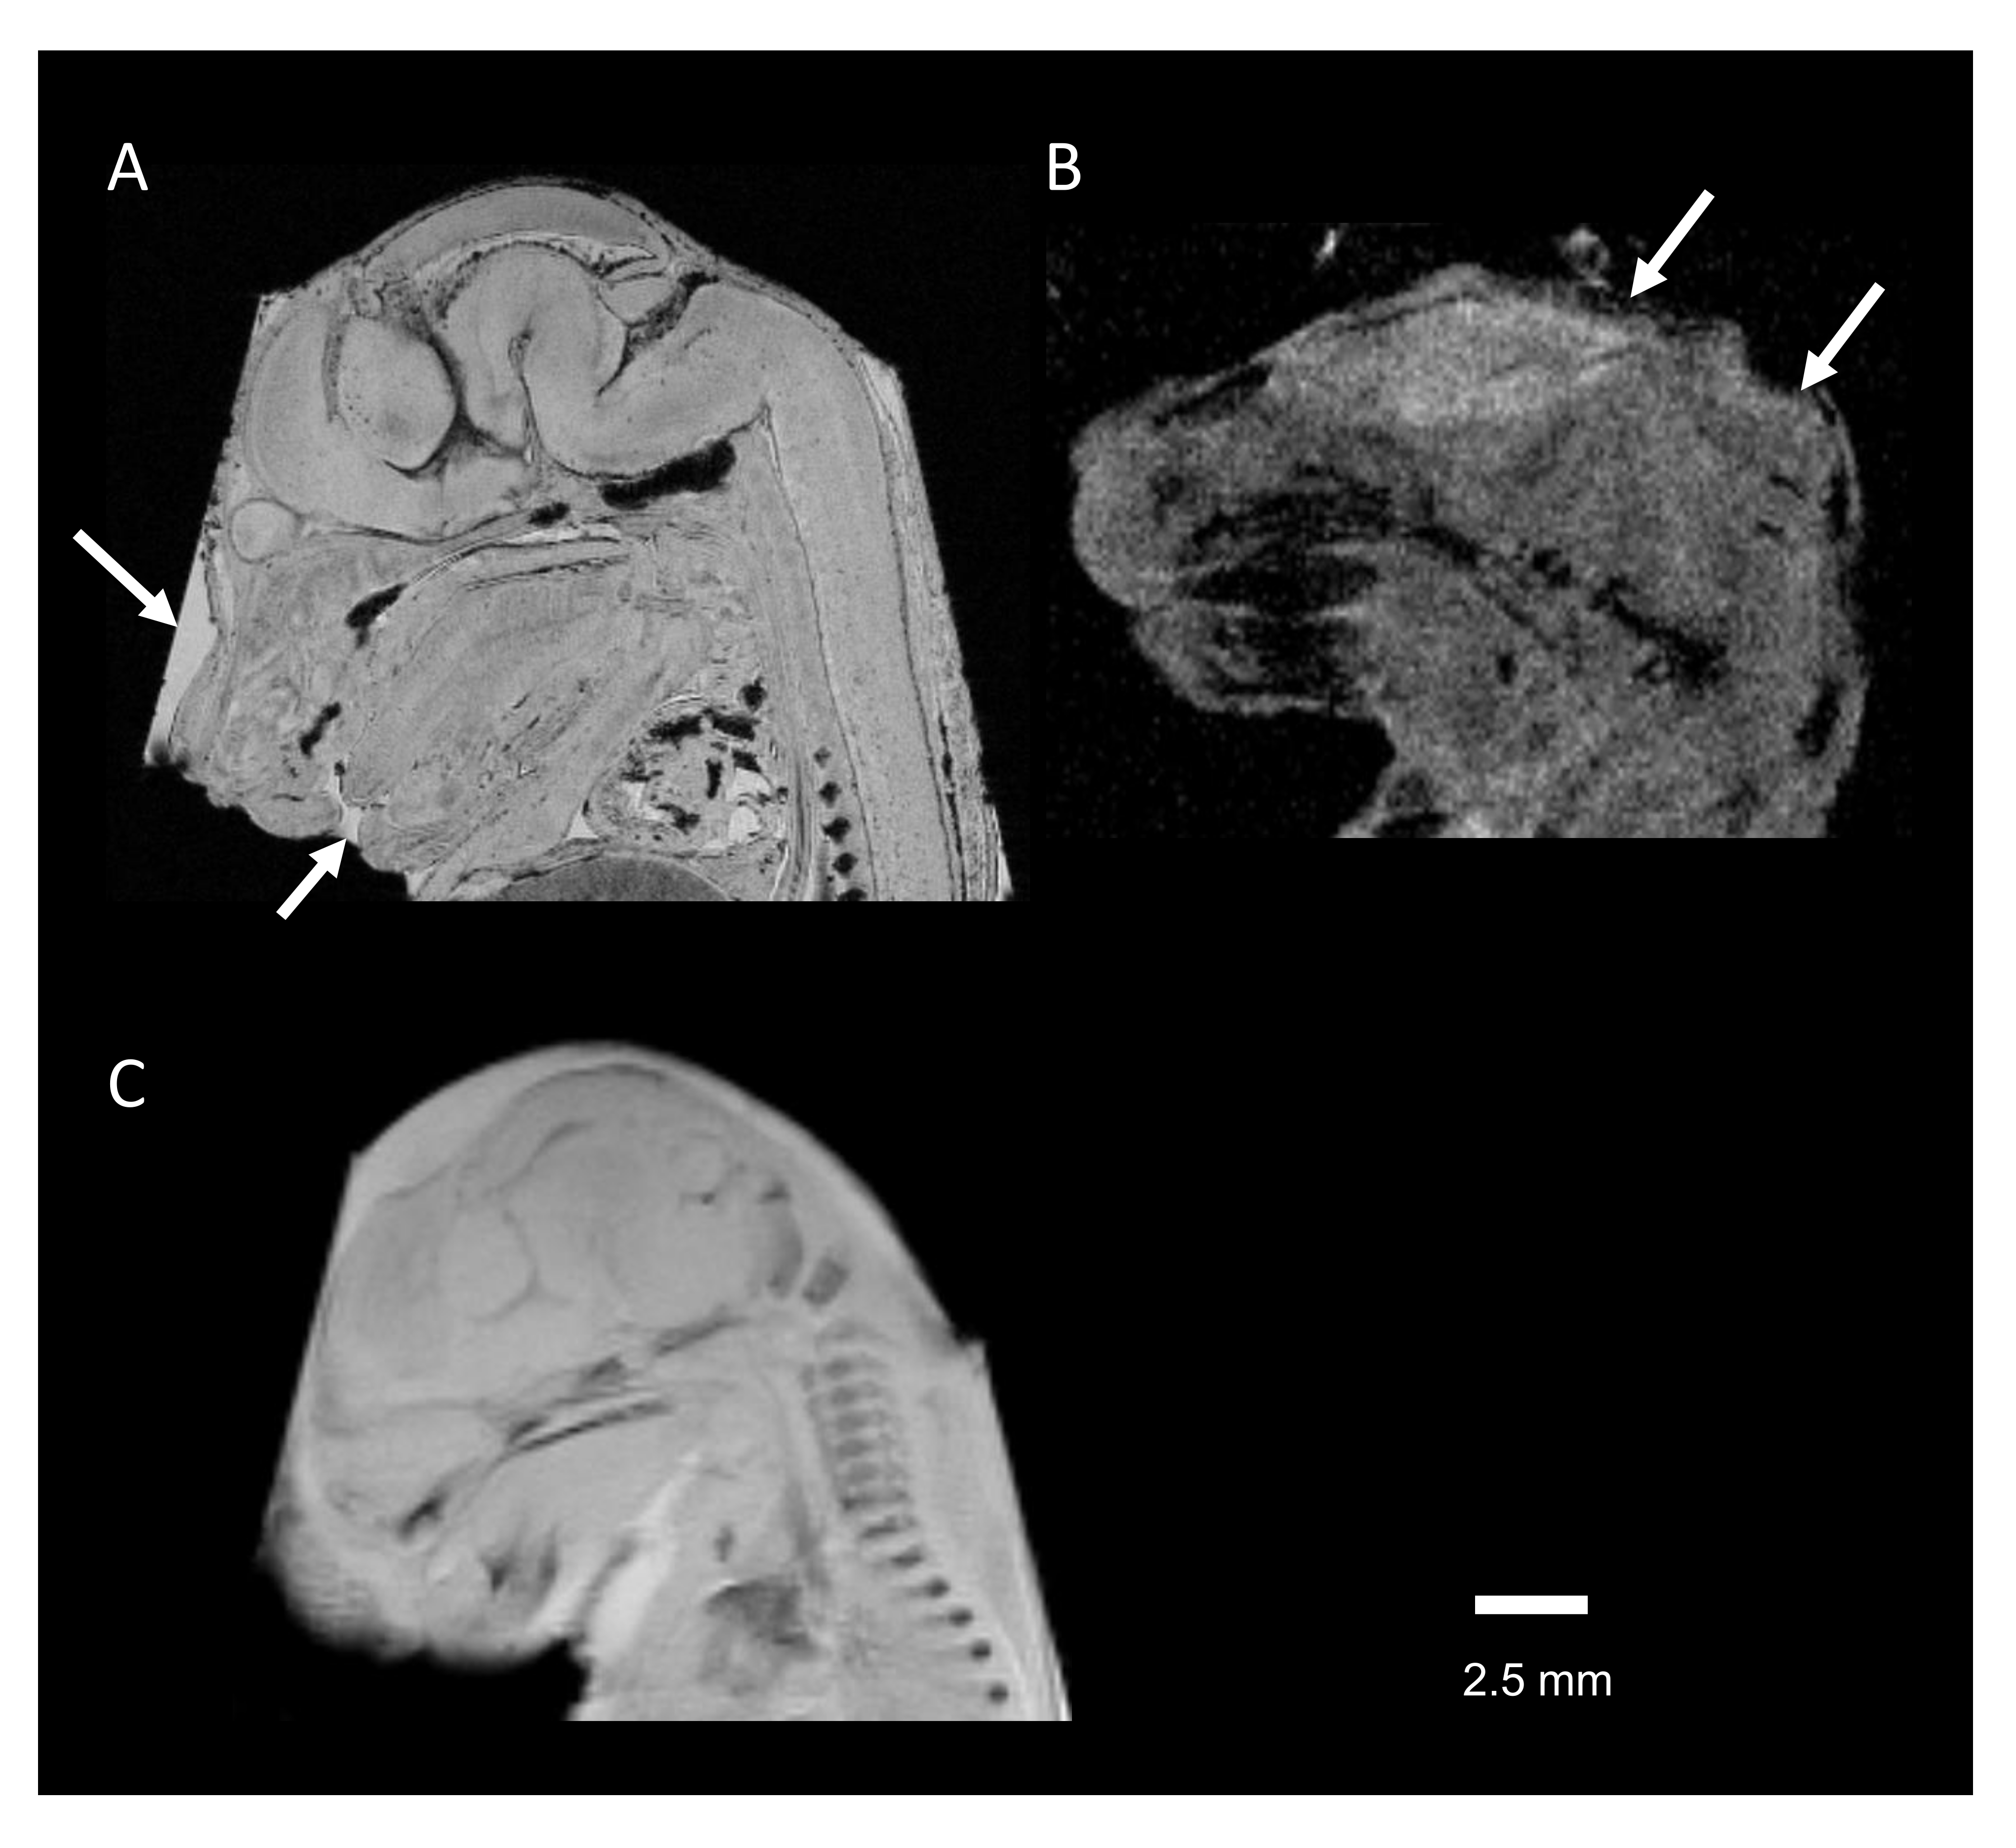

Figure 4 (A) Movement of the embryo body during 10 scans of T1-weighted imaging. Right figure shows the averaged T1-weighted image through 10 scans. (B) Movement of the embryo body during 10 scans of T2-weighted imaging. Right figure shows the averaged T2-weighted image through 10 scans.